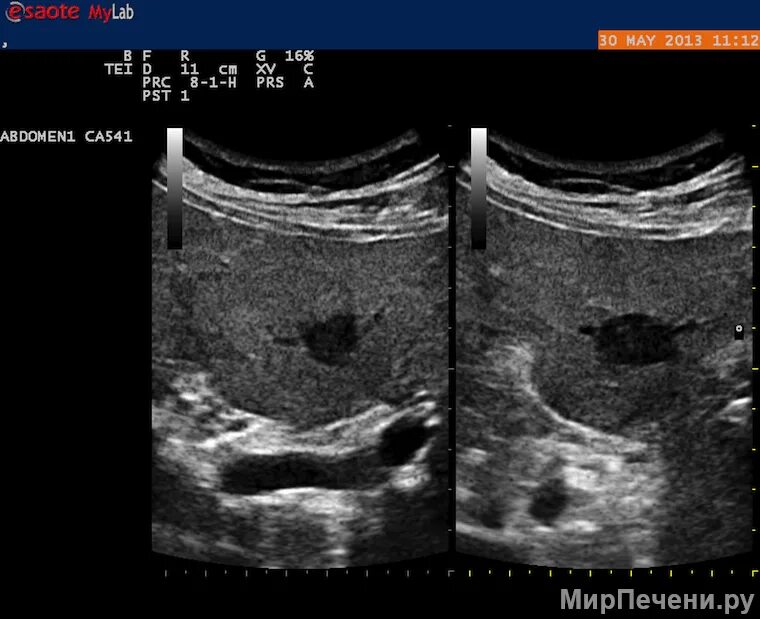

Скрининг кт